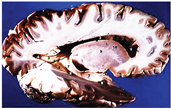

Table 2, Table 3, Table 4 and Table 5 present the results obtained through the multi-objective optimization image enhancement approach. Specifically, Table 2 and Table 3 show the results for natural images, while Table 4 and Table 5 display medical images. The tables are organized as follows: the first and second columns list the image names and their corresponding original, unenhanced versions. The third to fifth columns showcase the selected points from the Pareto front, representing the maximum contrast, knee point, and maximum detail, in that order. The final column illustrates the obtained Pareto front through the optimization process, with red, green, and orange points indicating the images that achieved maximum contrast, knee point, and maximum detail, respectively.

Table 4.

Medical image results—1.

As observed in the results, the images extracted from the Pareto front significantly maximize contrast and detail compared to the original images. In all study cases, the original image is dominated by the solutions extracted from the fronts, demonstrating the approach’s effectiveness in improving visual quality. However, the differences among the three enhanced images for each problem require a more detailed analysis.

For medical images, there are instances where differences are more perceptible. For example, in the Medical3 image, the maximum contrast solution makes it difficult to visualize the internal details of the basophil (a white blood cell highlighted in the box), which could result in a less accurate interpretation. In contrast, the knee and maximum detail solutions provide a clearer view of the interior of the white blood cell. Similarly, in the Medical5 image, the maximum contrast solution highlights the hand and arm bone structures. However, the maximum detail image offers a more precise view of the internal structures within the bones (see the highlighted region), which is crucial for a more detailed evaluation. Another notable example is the Medical8 image, where the maximum detail solution offers a more detailed view of the internal structure of the eosinophil (another type of white blood cell). However, the maximum contrast image improves the visibility of red blood cells. As shown in the yellow box, this solution reveals a red blood cell that is nearly imperceptible in the other solutions. An interesting case is the Medical6 image, where only a few non-dominated solutions are present on the Pareto front. Despite the similarities among the preferred solutions, the nodules are much more perceptible in the enhanced images than in the original image, as observed in the highlighted region.